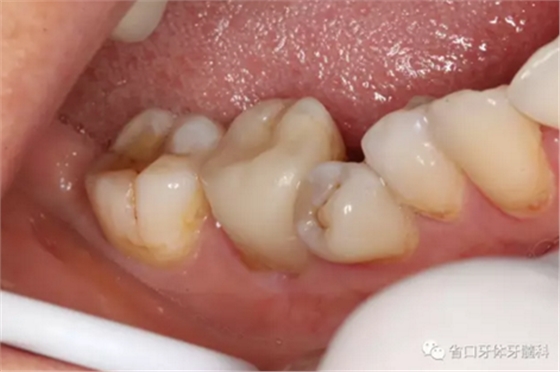

圖9-11 嵌體試戴粘接后,窩溝形態(tài)和、染色有待改進

圖12-14 術后1年回訪:無明顯食物嵌塞,咬合關系良好,牙周健康,未見瘺管

圖15-17 術后1年5個月回訪:患者使用良好,無明顯食物嵌塞,牙周健康,瘺管未見復發(fā)。